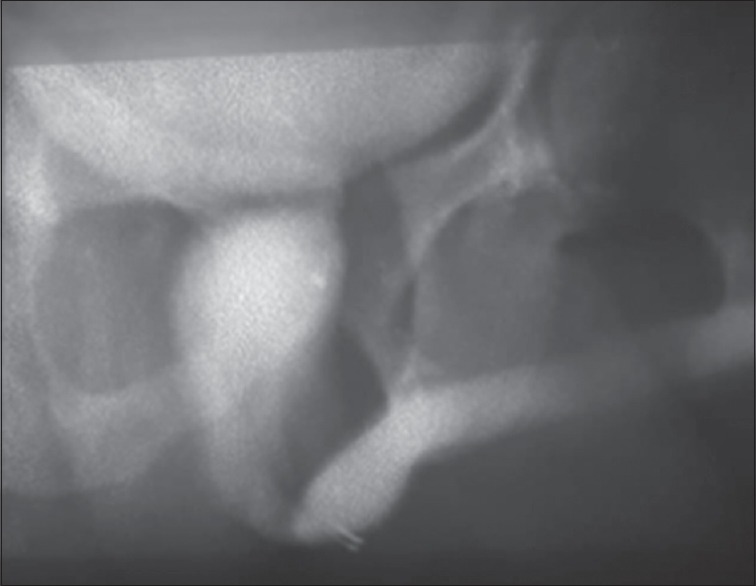

A 34-year-old civil servant presented to our facility, following a referral from a gynecologist who was also seeing the wife. The man presented with a history of anejaculation and the inability to impregnate his wife after 23 months of marriage. History, physical examination, and ancillary investigation led to a diagnosis of primary infertility secondary to posterior urethral valve which was subsequently ablated. Three weeks after ablation, he started ejaculating, and 2 months later, the wife became pregnant.

Abstract Image